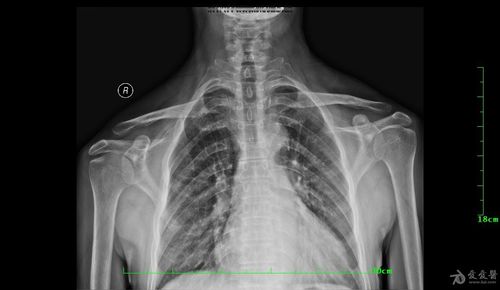

肩锁关节脱位分度,肩锁关节图片

肩锁关节脱位

肩锁关节图片

肩锁关节脱位图片

肩锁关节脱位三度图片

右肩锁关节脱位图片

肩锁关节脱位x线图片

肩锁关节脱位图片表现